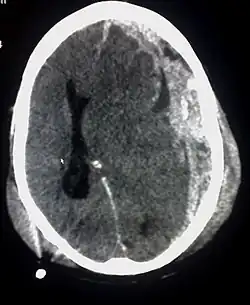

- stoornis in de bloedtoevoer naar de hersenen (bijvoorbeeld bij trombose, een hersenbloeding, cerebrovasculair accident (CVA) of hartstilstand)

- contusio cerebri (hersenkneuzing)